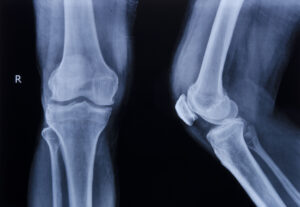

Not all fractures are created equal. Some will heal with a cast and a little bit of time and rest, while others may need surgery, pins, or plates, and they can still leave a person with chronic pain if they don’t heal properly.

These long-term impacts don’t always show up on X-rays, but they’re just as real as the physical break, and they can reshape your life in ways no one expects.